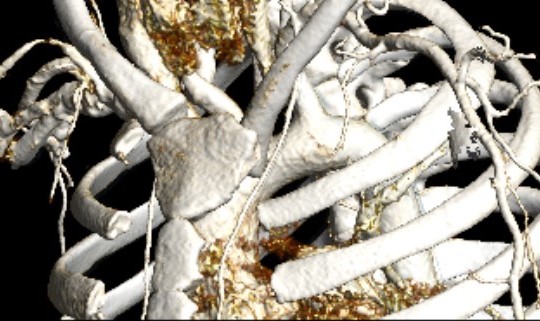

CT scan

Left posterior SCJ dislocation with pre- and post angiogram

Severe left posterior SCJ dislocation with subclavian vein compression